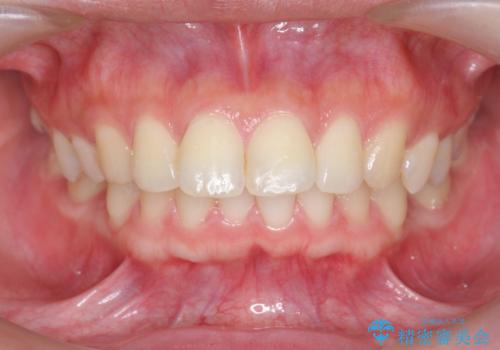

カリエール・マイクロインプラントを併用した歯の突出を改善する大きな遠心移動

- 口が閉じづらく、突出し歯が出っ歯に見えてしまうことの改善を求めて来院されました。

カリエール・マイクロインプラントを用い、時間はかかりましたが大きく歯の後方移動が達成され、前歯の見た目が大きく改善されました。